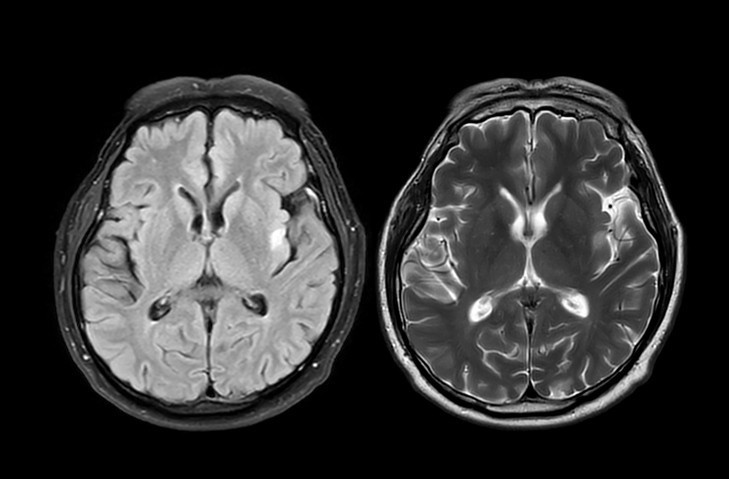

Alzheimer’da özellikle tau ve amiloid beta adı verilen proteinlerin beyinde anormal şekilde birikmesi büyük önem taşıyor. Bu birikimler sinir hücrelerinin işleyişini bozuyor ve zamanla hastalığın ilerlemesine katkıda bulunuyor.